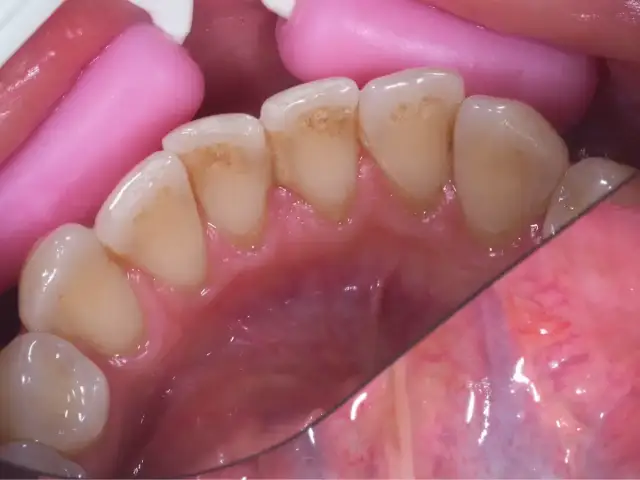

Skaling zębów - efekty przed i po, czy zęby będą bielsze?

Skaling zębów - poznaj realne efekty przed i po. Czy boli? Czy zęby będą jaśniejsze? Sprawdź, jak dbać o uśmiech i kiedy go wykonać.